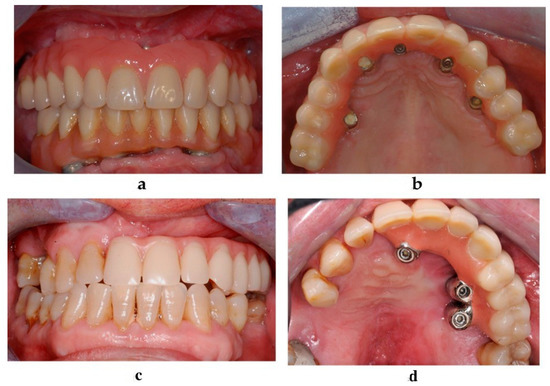

Figure 5. Orthopantomographic evaluation at 4 and 5 years after the surgery in the atrophic group (a) and in the oncologic group (b).

Radiologic examination included an orthopantomographic examination (Figure 5a,b) every year and a lateral teleradiographic examination after implant loading. A CBCT examination was performed at 1 year after the surgery and was repeated if needed. All patients underwent a strict professional hygiene maintenance protocol with 3-month recalls. Instructions and devices for maintaining proper oral hygiene at home were provided to the patients.